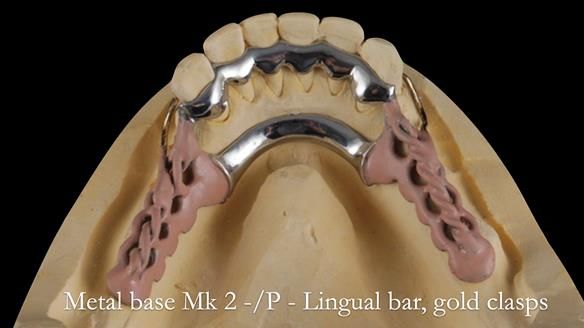

This newsletter describes the full protocol workflow of a complete upper denture and a lower partial denture for Jo.

- The forces placed on the teeth are large (bruxism). This will make the dentures proposed in the treatment plan below wear, chip and break more quickly. Therefore, the final dentures will require metal reinforcement to make them as robust as possible.

The clinical situation and treatment process is shown in detail below. I provided the clinical work. Rowan Garstang provided the technical work. This treatment took 25 visits over a period of 12 months.